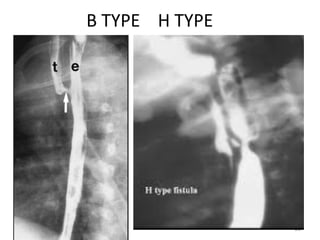

B TYPE H TYPE

C A E B D

Classification (Gross's Anatomical

Classification)

• Type A: isolated Esophageal atresia(8%).

• Type B: proximal fistula with distal atresia.

• Type C: proximal atresia with distal

tracheoesophageal fistula (most common

type) (85%).

• Type D: Esophageal atresia with proximal and

distal fistula.

• Type E: isolated fistula without atresia(4%)